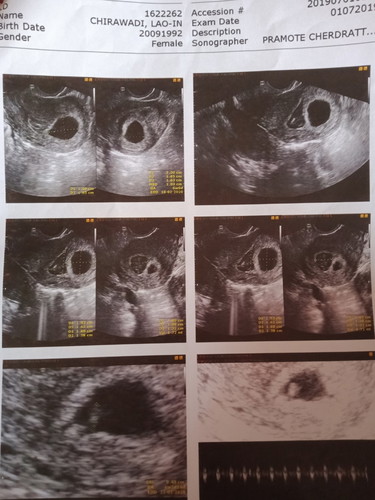

แวะมาขอกำลังใจแม่ๆค่ะ 6w4d วันที่1 กค. มีเลือดออก ไปซาวด์ดู น้องยังอยู่ มีหัวใจเต้น หมอฉีดยากันแท้งให้ หมอบอกว่า น้องมีภาวะรกลอกตัว ทำให้เลือดออก ถ้าลอกตัวสำเร็จ คือแท้งค่ะ ตอนนี้แม่ต้องลางานมานอนนิ่งๆ 7 วัน วันนี้เข้าวันที่4 แล้ว เลือดก็หยุดไหลแล้ว หมอนัดตรวจติดตามผล วันจันทร์หน้า น้องจะยังปลอดภัย และปกติดีไหมคะแม่ๆ แม่กังวลใจมาก เป็นห่วงน้อง กลัวน้องหยุดการเจริญเติบโต...

#แม่เจ้าของโพสต์วันนั้นเองค่ะ# 😃❤️ ขอบคุณกำลังใจจากแม่ๆทุกคนนะคะ แม่หยุดงานไปทั้งหมด 1เดือนเต็มค่ะ เพราะ7วันไม่พอจริงๆค่ะ พอฉีดยากันแท้งครบ7วันเลือดออกมาเพิ่มอีก ทีนี้สีแดงสดและเยอะ เลยตัดสินใจย้ายไปฝากครรภ์ที่คลินิกและหมอให้ยากันแท้งมาทานทุกๆ8ชม. จนกว่าเลือดจะหยุดไหล ระหว่างนี้แม่เทียวหาหมอบ่อยมาก อัลตราซาวด์ทุกครั้งเพื่อเช็คว่าลูกยังมีหัวใจเต้นอยู่ไหม..จนแม่หมดเงินไปเยอะมากค่ะ บางที3 วันไปหาหมอ1ครั้ง เพราะความกังวลและห่วงลูก.. เลือดหายสนิทช่วงตั้งครรภ์ได้ประมาณ3เดือนค่ะ .. ตอนนี้น้องได้ 28 วีคแล้วค่ะ ได้ลูกสาวค่ะ ลูกคงรู้ว่าแม่สู้มาก อยากขอบคุณกำลังใจจากแม่ๆทุกคนนะคะ และอยากขอบคุณตัวเล็กที่สู้ไปกับแม่... 🙏😃💕❤️

เราซาวด์ 5 week ไม่เจอน้องเจอแต่ถุงน้ำ มีผนังมดลูกลอกตัว กังวลมากเรื่องครรภ์ไข่ปลาอุก หลังจากนั้น 2-3 วัน มีเลือดออก ยังทนอยู่นะคะ เพราะคิดว่าเลือดล้างหน้าเด็ก พอ 6 week ถึงไปหาหมอพอ ซาวด์ถึงเจอถุงตั้งครรภ์กับน้อง ช่วง 6-12 week มีเลือดออกกระปริดกะปอย ตลอดเลยคะ ฉีดยากันแท้ง 1 เข็ม ตอนนี้ 38 week แล้วคะ ยอมรับความเครียด กับการพักผ่อนมีผลกับร่างกายคุณแม่มาก ขอให้ผ่านไปด้วยดี เหมือนเรานะคะ